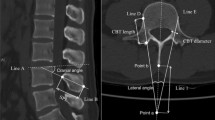

The pedicle and iliac screw placements were assessed for cortical breaches on the intraoperative 3D CBCT and postoperative CT images for the ARSN and the FH groups, respectively. Three independent reviewers, two neuroradiologists and one orthopedic spine surgeon, performed the assessment. The Gertzbein scale was used to evaluate the clinical accuracy: grade 0 (no cortical breach), grade 1 (0–2 mm breach, minor perforation including cortical encroachment), grade 2 (>2–4 mm breach, moderate breach) and grade 3 (>4 mm breach, i.e. severe displacement)12. Screws assessed as Gertzbein grade 0 and 1 were considered accurately placed. Direction of breaches larger than 2 mm were documented. The assessment was performed in multi-planar views along the axis of the screw. Figure 3 depicts an example of a screw assessed under CBCT and CT for the ARSN and free-hand group, respectively13.

Examples of multi-planar images displayed according to each screw axis for screw position assessment. On the left, rating performed on an intraoperative cone beam CT of a patient treated with augmented reality surgical navigation (ARSN). On the right, rating performed on a postoperative CT of a patient treated with the free-hand (FH) technique.